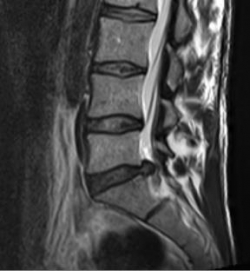

MRI with lateral reconstruction of the lumbar spine. In the area of the lowest intervertebral disc, a protrusion of the intervertebral disc to the right (back) can be seen